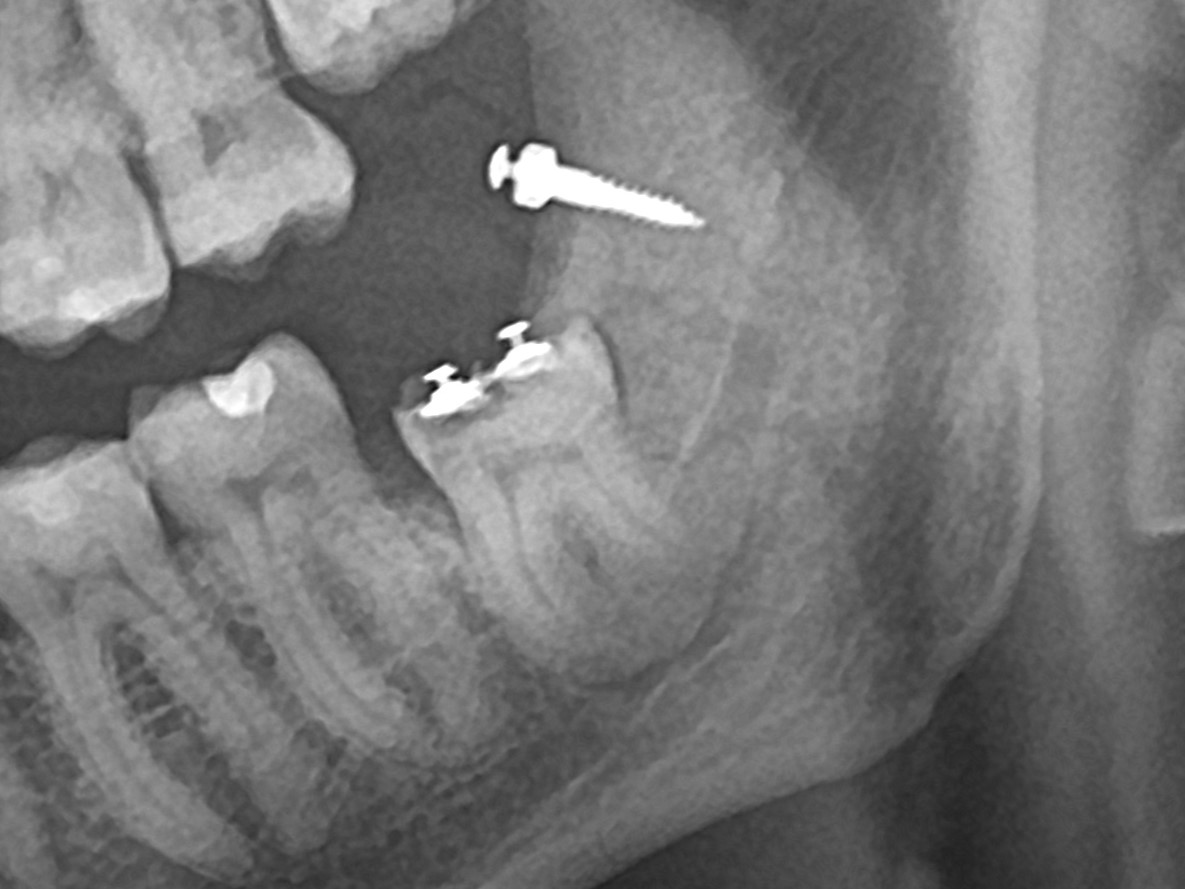

К 14-й неделе лечения на ОПТГ было зафиксировано значительное  смещение  зуба, достаточное для его удаления.

ОПТГ на 14 неделе